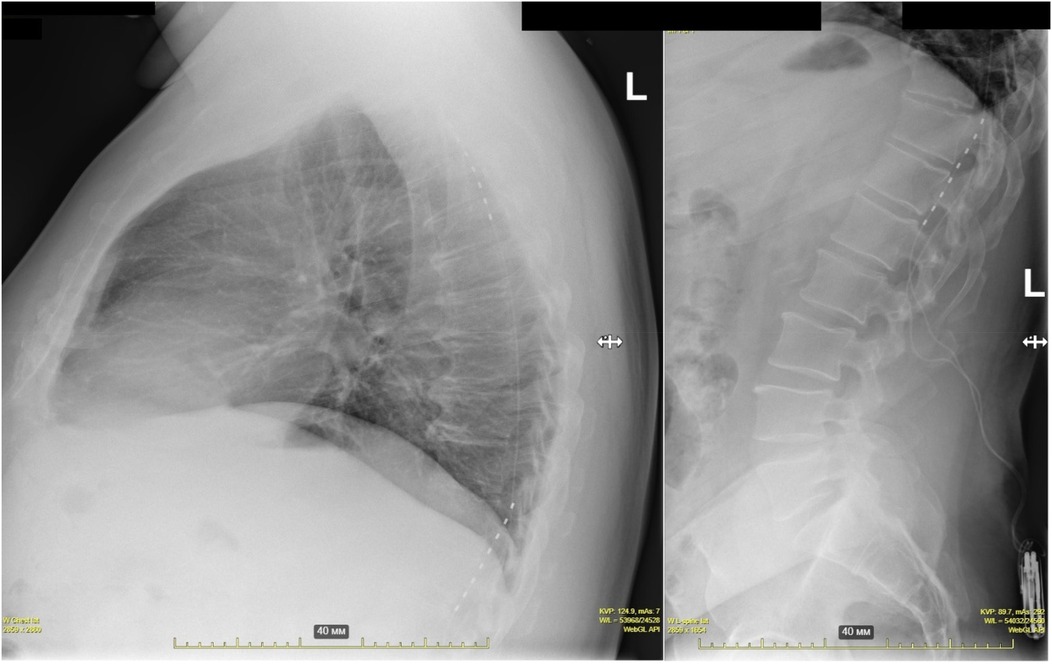

Background: Refractory angina pectoris represents a significant clinical challenge characterized by persistent chest pain despite maximally tolerated medical therapy and optimal revascularization attempts. This study evaluates the efficacy and safety of invasive spinal cord stimulation (SCS) in patients with refractory angina. Methods: Twenty-one patients underwent neurostimulation system implantation between 2022 and 2023 (mean age 62.8±7, 12 males) diagnosed with refractory angina. All patients received both chronic continuous stimulation and on-demand stimulation to alleviate anginal pain episodes. The primary endpoint was changes in the Seattle Angina Questionnaire (SAQ-19) scores. Secondary endpoints included changes in the Short Form Health Survey (SF-36), incidence of major adverse cardiovascular events, device-related complications, and nitrate use. Results: Eighteen patients completed the final follow-up. No statistically significant improvements were observed in any SAQ-19 domains. However, reductions in pain scores (41% vs. 53%, p=0.007) and improvements in mental health scores (61% vs 72%, p=0.021) and physical functionating (36 vs 52%, p = 0.017) were noted on the SF-36. Device extraction occurred in three cases (14%) - two due to pocket infection and one at the patient's request. Four lead repositioning procedures were performed (19%). Hospitalization rates significantly decreased over the one-year observation period, from 3.8 to 0.5 hospitalizations per patient (p=0.03). Recurrent acute coronary syndrome was noted in one patient, requiring additional coronary stentings. Notably, although no significant reduction in nitrate therapy was achieved, the treatment regimen prevented any new nitrate prescriptions during the study period. Conclusion: SCS did not significantly improve the primary endpoint of disease-specific quality of life (SAQ-19). However, treatment was associated with secondary benefits, including improvements in physical functionating, pain and mental health (SF-36) and a significant reduction in hospitalization rates. Complication rates were significant.